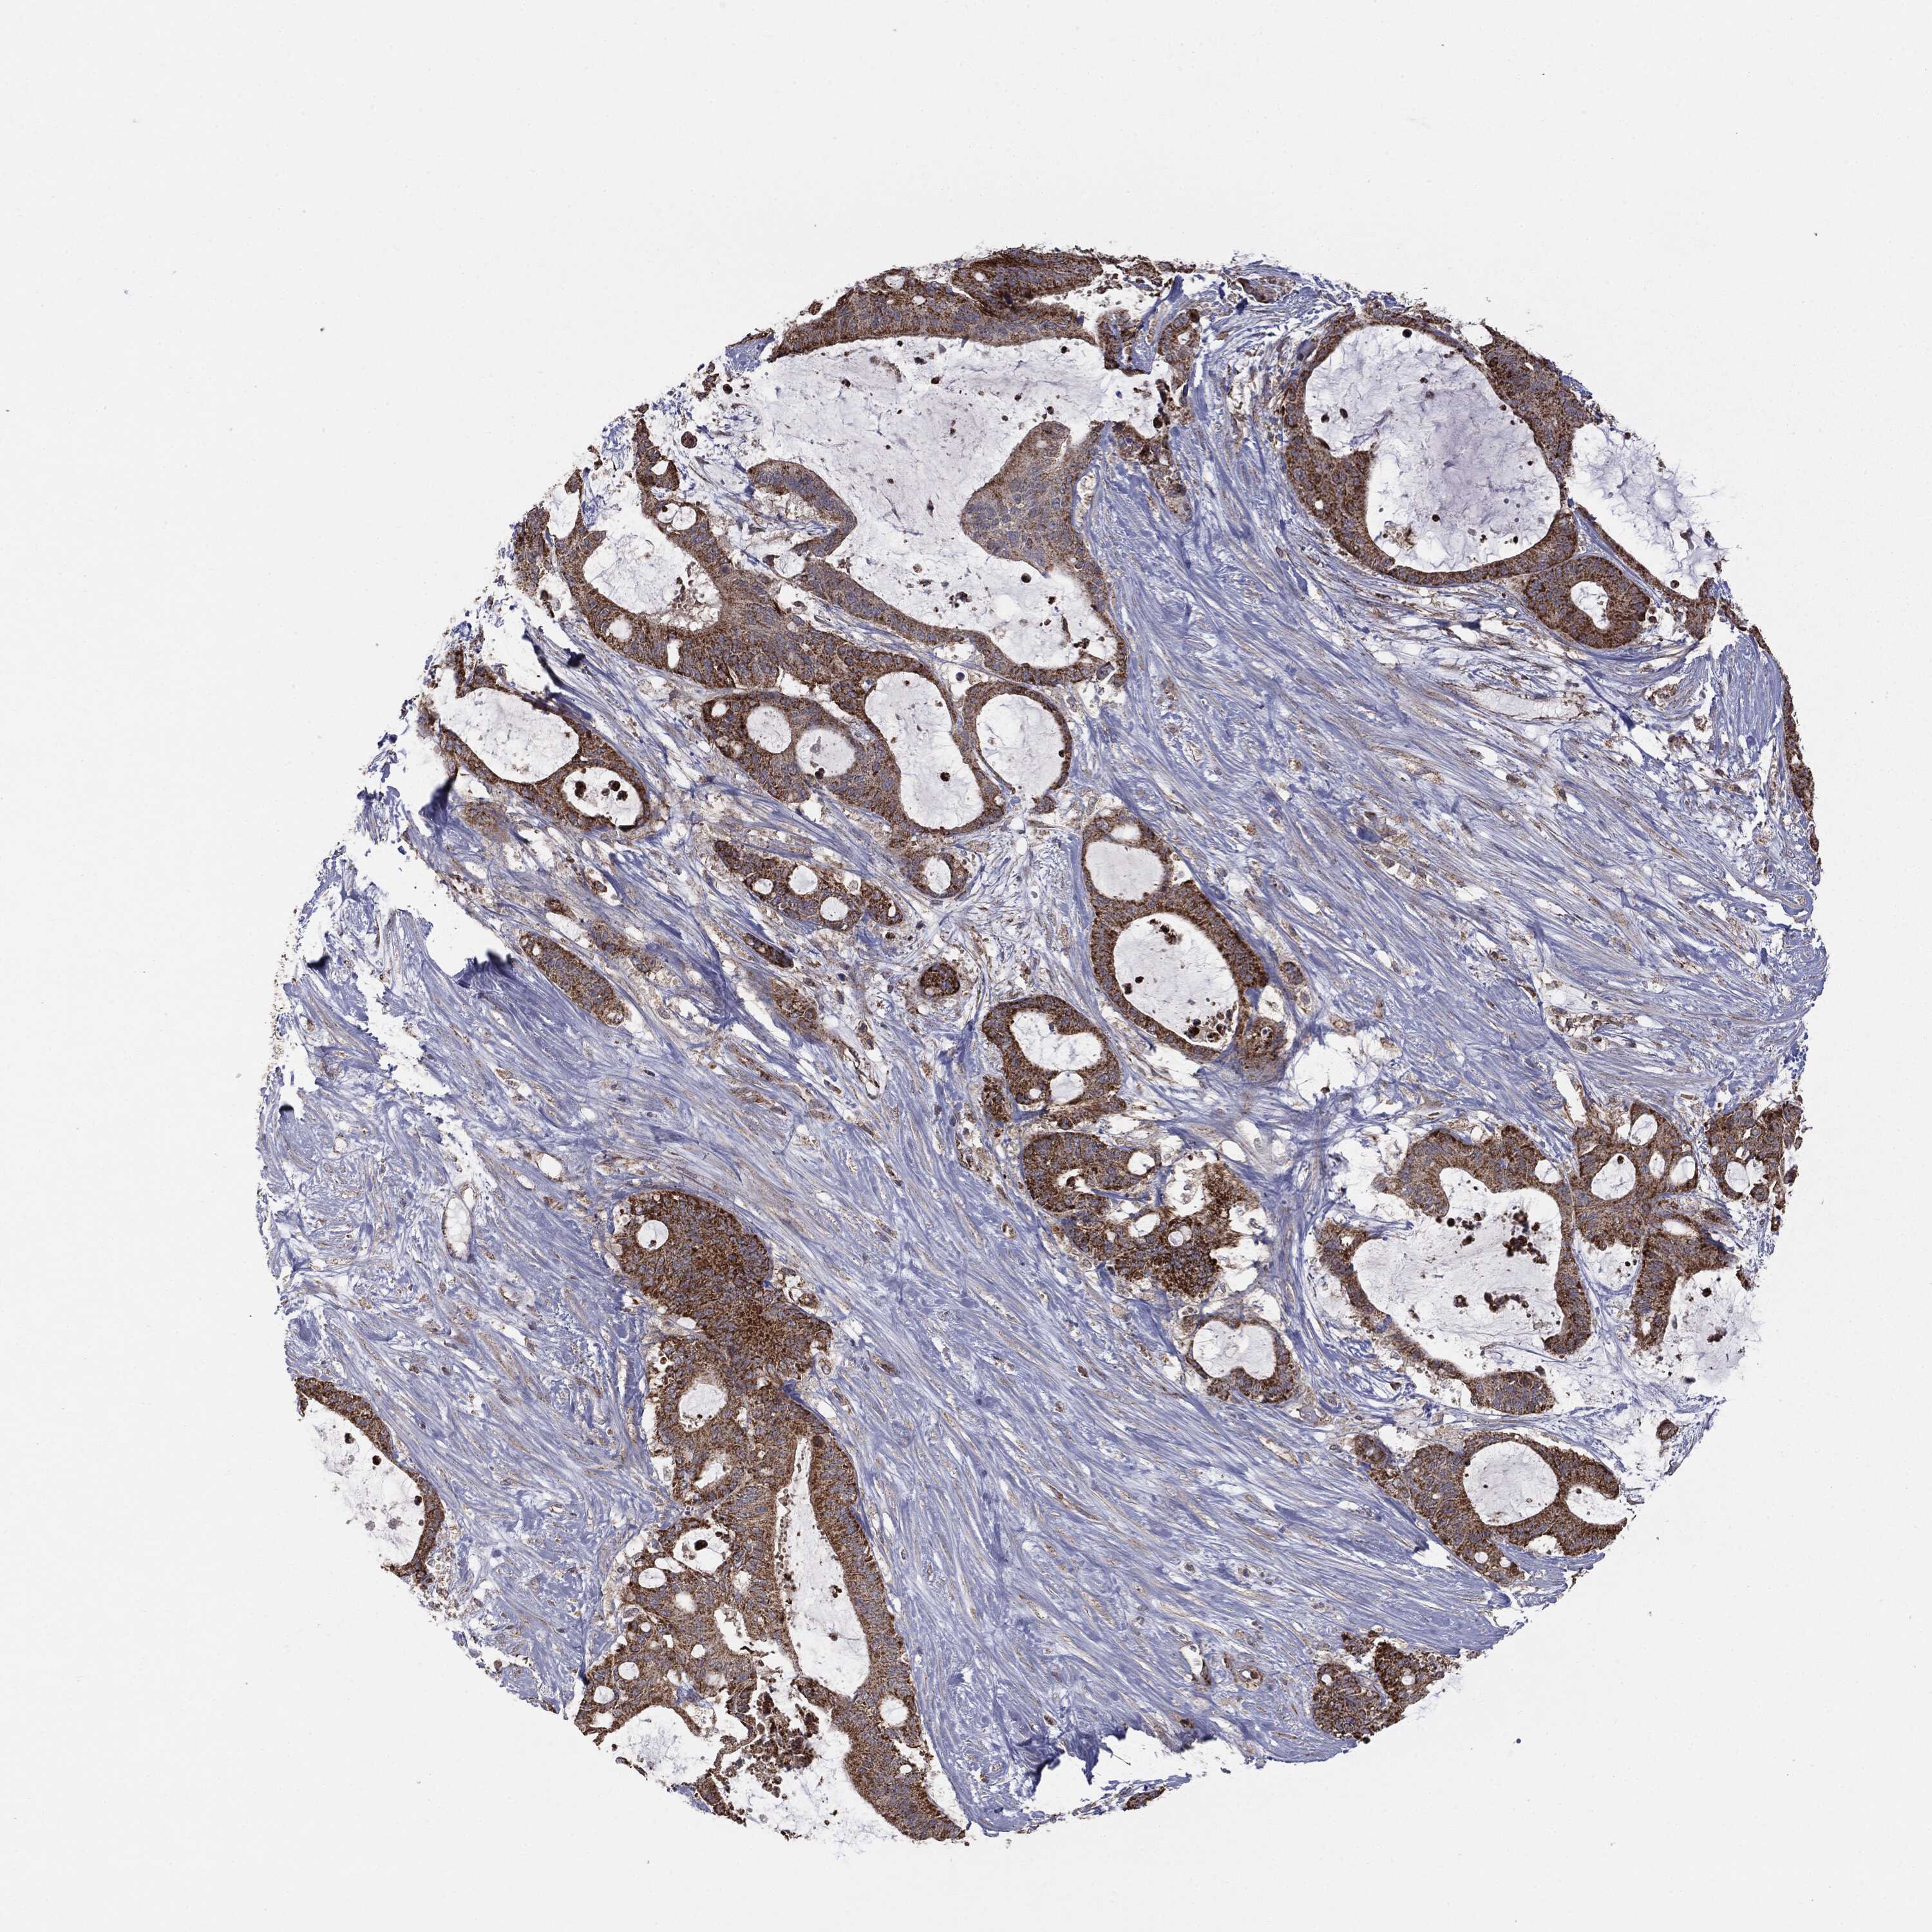

LIVER CANCER - Protein expressioni

A mouse-over function shows sample information and annotation data. Click on an image to view it in a full screen mode. Samples can be filtered based on level of antibody staining by selecting one or several of the following categories: high, medium, low and not detected. The assay and annotation is described here.

Note that samples used for immunohistochemistry by the Human Protein Atlas do not correspond to samples in the TCGA dataset.

Antibody stainingi

Antibody staining in the annotated cell types in the current human tissue is reported as not detected, low, medium, or high, based on conventional immunohistochemistry profiling in selected tissues. This score is based on the combination of the staining intensity and fraction of stained cells.

Each image is clickable and will lead to virtual microscopy that enables deeper exploration of all samples and also displays staining intensity scores, fraction scores and subcellular localization as well as patient and tissue information for each sample.

Cholangiocarcinoma